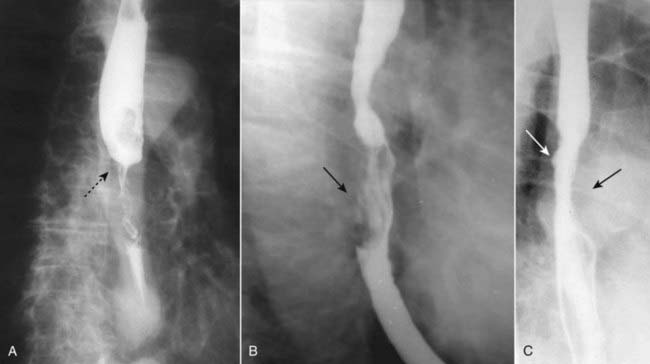

Figure 18-4 Esophageal carcinomas.

Three different patients are shown with different appearances of esophageal carcinoma. A, There is an annular constricting lesion of the mid-esophagus (dotted black arrow)—the tumor encircles the normal lumen and obstructs it, in this case. B, A polypoid mass that arises from the right lateral wall of the esophagus displaces the barium around it (solid black arrow). C, The wall is irregular and rigid and contains a small ulceration (solid white arrow); the aortic knob is producing a normal indentation on the opposite wall of the esophagus (solid black arrow).